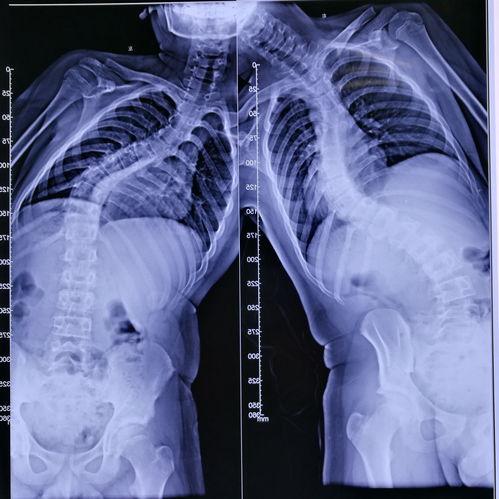

手术开始了,医生首先在女孩的背部切开一个小口,然后插入一根细长的金属棒。这根金属棒将贯穿整个脊柱,起到支撑和矫正的作用。接下来,医生在金属棒的两侧分别安装了两个金属钩,将它们固定在女孩的脊椎骨上。

随后,医生开始调整金属钩的位置,使脊柱恢复到正常状态。这一过程需要精确的操作,因为任何一点偏差都可能导致手术失败。经过一番努力,医生终于将脊柱矫正到理想的位置。

接下来,医生将金属棒与金属钩连接起来,形成一个稳定的支架。医生在手术切口处缝合,手术宣告成功。